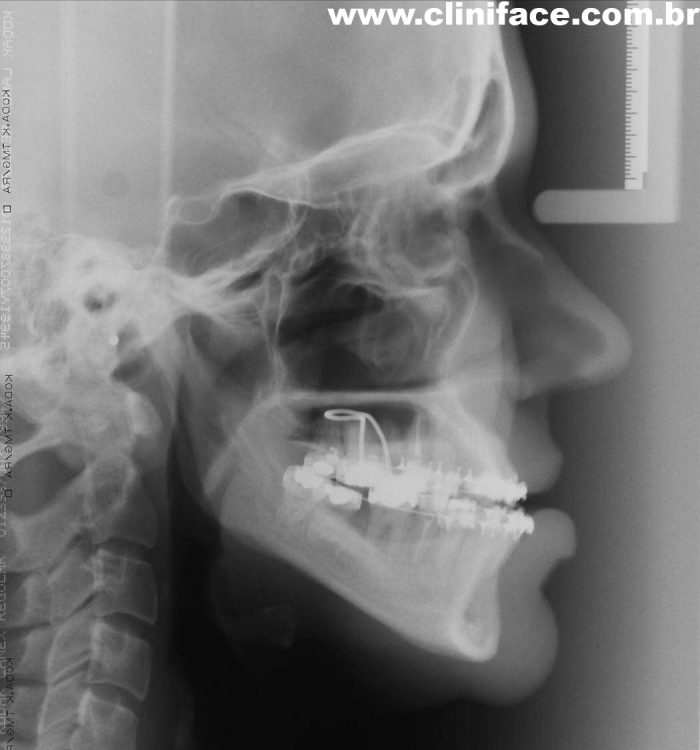

Telerradiografia final - Clínica Cliniface

Telerradiografia final